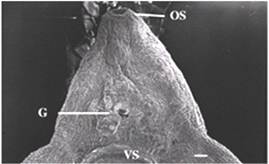

Để hiểu biết về cơ chế kháng thuốc TCBZ diễn ra như thế nào thì điều trước tiên cần thiết là phải biết được cơ chế tác dụng của thuốc.TCBZ là một dẫn chất thuộc nhóm benzimidazole và là analogy các chất thuộc nhóm thuốc benzimidazole, người ta cũng đã đoán trước liệu rằng TCBZ có thể gắn với phân tử β-tubulin và làm dừng quá trình tác động trên trên vi quản (microtubule). Các bằng chứng làm rõ và hỗ trợ cho quan điểm này dựa trên các bằng chứng nghiên cứu về mặt hình thái học (morphology) trên vỏ vi quản (tegument), tuyến noãn hoàn (vitellaria) và tinh hoàn (testis) khi điều trị bằng chất chuyển hóa sulphoxide của triclabendazole (TCBZ.SO). Chẳng hạn, có sự ức chế quá trình phân bào bên trong tuyến noãn hoàng và các tế bào sinh tinh (Stitt và Fairweather và cs., 1996); làm gián đoạn quá trình vận chuyển bên trong vi vỏ (lớp ngoài cùng của sán), dẫn đến tổn thương tiến triển nghiêm trọng bề mặt của vỏ sán và hậu quả cuối cùng là hủy mất toàn bộ cấu trúc vi vỏ (Stitt và Fairweather., 1994). Mất hình ảnh của vỏ ống qua hình ảnh nhuộm miễn dịch trong hợp bào ống cũng được quan sát (Robinson và cs., 2002; McConville và cs., 2006) (hình 1 và 2). Các kết quả trên cho thấy rằng các vi quản biến mất, ngăn cản sự chuyển động của các vật thể tiết từ các tế bào trên bề mặt của vi vỏ. Tiến trình này là duy trì sự sống còn và toàn vẹn của màng bề mặt cũng như sự gián đoạn như thế sẽ giải thích cho những thay đổi về hình thái học rất nghiêm trọng.

| |

Hinh 1: dải băng đậm vỏ sán nằm bên dưới cấu trúc màng bào tương Và bên trênmàng đáy (B). Hợp bào gần gai (S) cho hình ảnhphát quang. | Hình 2: Những con sán nhạy cảm với TCBZ (liều 15μg/ml/24 giờ) dải băng phát quang nhạt bên dưới apm và bên trên trụ gai (S). |